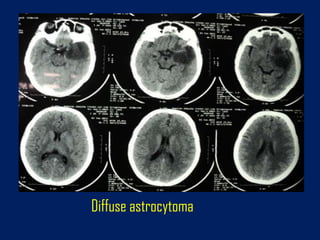

Diffuse astrocytoma